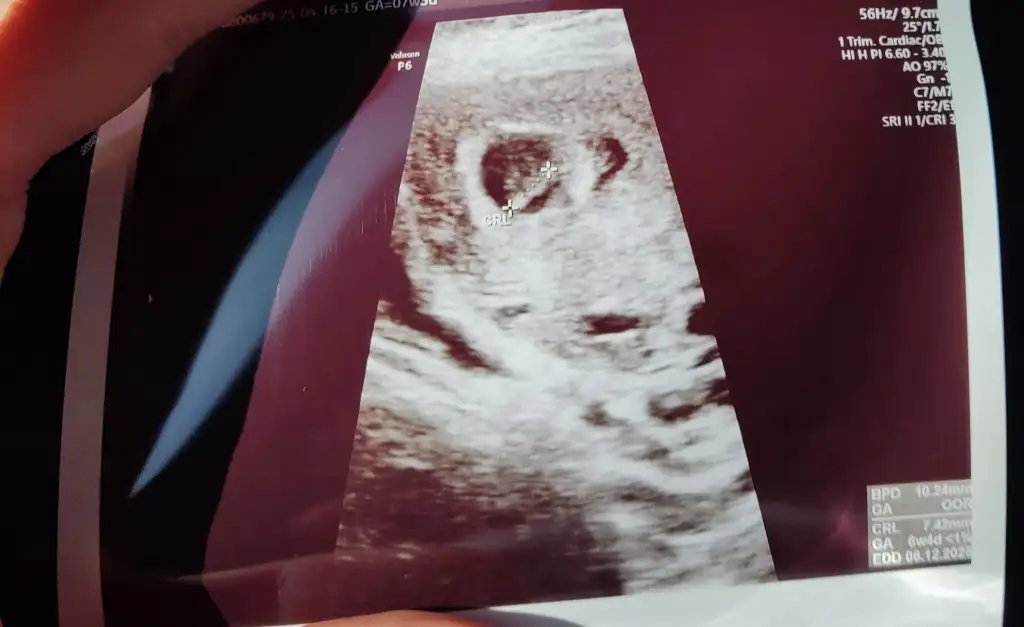

Bana da yorum yapabilir misiniz kızlar 7. Haftadan abdominal goruntu

• IMG_3202.webp

IMG_3202.webp

50 KB · Görüntüleme: 70

Abdominal görüntüyse eğer kız olabilir ☺️🌸 ama sanki sizin ultrason görüntünüz ters gibi . Normalde dar olan kısım yukarda geniş olan kısım aşağıda olur. Bilemedim bu bebişe karar vermek zor çünkü görüntü tam tersiyse eğer erkek de olabilir ☺️ sağlıkla gelsin. Daha net bir görüntü olursa paylaşın ☺️